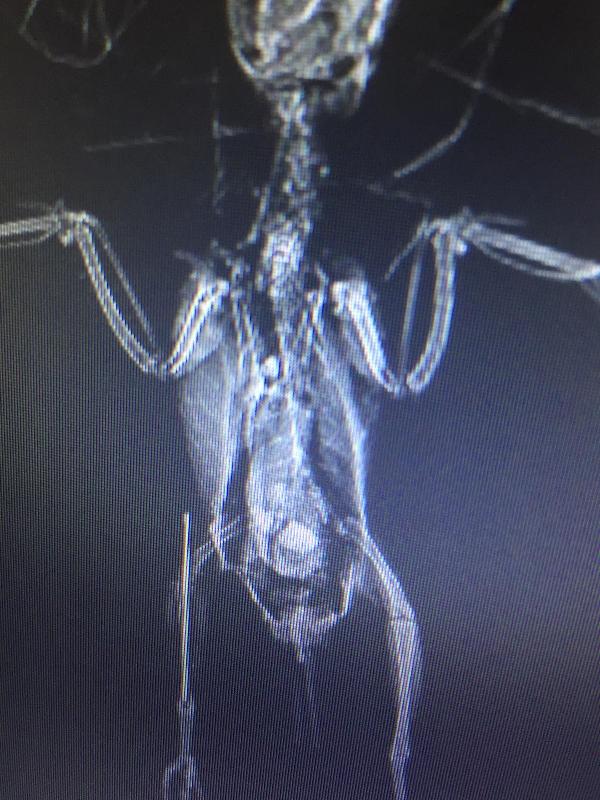

Petshop sahibi Ali Kaya, muhabbet kuşunun sağ ayağında şişlik olduğunu fark edince özel veteriner kliniğine götürdü. Kuşun çekilen röntgeninde sağ ayağında kırık tespit edildi. Veteriner hekim Önder Alkan, kuşu ameliyata alarak ayağına pim yerleştirdi. 2 saat süren ameliyatın ardından kuşun 1 ay içerisinde yürüyebileceği söylendi. Ameliyatın başarılı geçtiğini söyleyen Alkan, "Muhabbet kuşu sağ bacağında şişlik şikayetiyle bize getirildi. Ancak çekilen röntgen ile sağ ayağında kırık olduğunu tespit ettik. Kuş 20 gram civarında olduğu için gaz anestezi ile ameliyat yaptık. Ameliyatta kırık olan bacağını pim taktık. Başarılı bir ameliyat oldu. Ameliyattan sonra normal fonksiyonlarını yerine getirdi. Şu anda yemesi içmesi düzgün gidiyor.1 ay içerisinde yürüyüp tırmanma yapabilir." dedi.